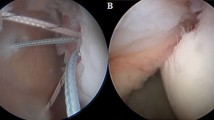

Three remplissage techniques were used (see Fig. 1):

Technique 1 (T1), as originally described by Purchase et al., was performed by inserting 2 double-loaded 5.5-mm anchors (Biocorkscrew, Arthrex Inc., Naples, USA) into the valley of the Hill-Sachs defect and passing horizontal mattress sutures through the infraspinatus tendon with surgical knots over the anchors [21].

Technique 2 (T2) involved placing of the anchors and passing of the sutures as in T1; however, sutures were tied using the double pulley technique described by Koo and Burkhart [22]. For T1 and T2, the pressure sensitive film was placed after the insertion of both anchors and passage of sutures through the infraspinatus tendon. Sutures were then tied to effect compression of the infraspinatus tendon and posterior capsule.

Technique 3 (T3) involved placement of two 4.75 mm knotless anchors (Swivel Lock, Arthrex Inc., Naples, USA) in the valley of the Hill-Sachs defect. The first knotless anchor was inserted with one end of a suture tape (Fibertape, Arthrex Inc., Naples, USA) and the tape was passed through the infraspinatus. The next knotless anchor was then inserted together with the tape through the infraspinatus tendon and into the valley of the Hill-Sachs defect. After pre-tensioning of the tape, by inserting the anchor according to the manufacturers recommendation, the tape was evenly tensioned. For T3 the pressure sensitive film was adhered to the defect before placement of the second knotless anchor. Care was taken to ensure that the second knotless anchor did not touch the pressure sensitive film. Subsequently the inferior capsule was repaired with sutures.